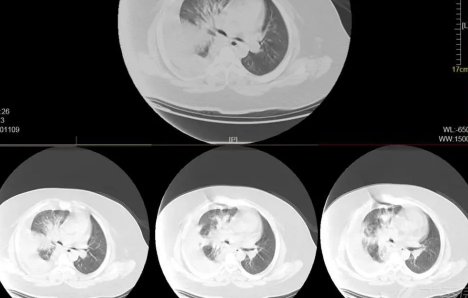

如果出现白肺,患者可能会出现一些严重的呼吸道症状,包括咳嗽、喘息、呼吸困难或体力活动时呼吸短促。一个更客观的指标是病人的呼吸频率,通常大于每分钟30次呼吸,或血氧饱和度低于93%就要警惕出现严重肺部感染。白肺并不能预防,只能预警。

肺白了一般是指白肺,白肺能否恢复与疾病类型、严重程度有一定关系,有些患者在检查时,发现肺白密度增高,如果是轻度肺部炎症引起的白肺一般是可以恢复的,如果是严重肺部炎症或肺间质纤维化引起的,则可能无法恢复。

如果是轻度肺炎引起的白肺,一般不用太担心,只要积极消炎治疗就可以了,一般炎症消退后,肺部就可以恢复健康,在日常生活中也要注意避免吸烟,避免长时间呆在空气肮脏的环境中。

如果是比较严重的肺炎或肺间质纤维化引起的白肺,一般会伴有呼吸困难的症状,首先应该改善患者的呼吸状态,可以帮助患者通过吸氧呼吸,也应该使用抗生素类药物进行治疗,症状消退后,白肺症状会相应减轻,但一般不会完全恢复。

此外,白肺也可能由肺结核、肺肿瘤等原因引起,需要鉴别诊断。